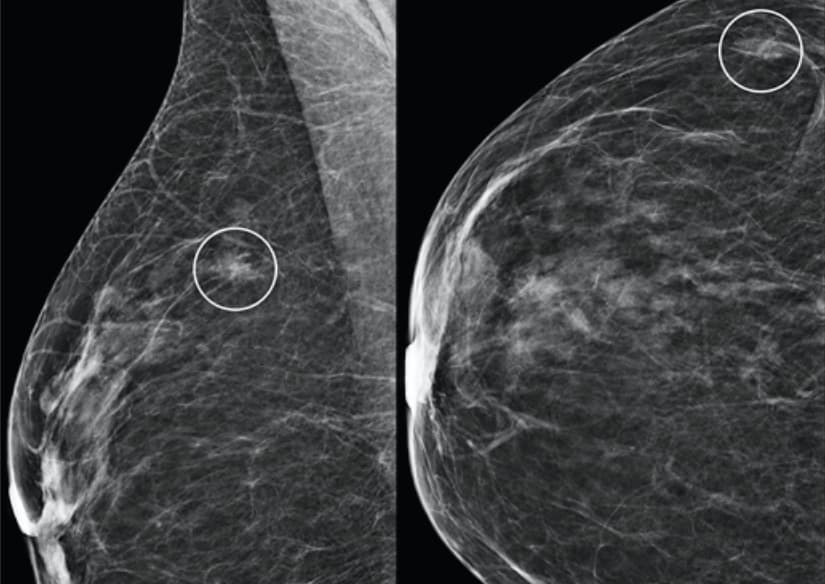

Une stratification plus robuste du risque de cancer du sein avec l'IA

Un modèle d'IA basé uniquement sur l'analyse d'images pour prédire le risque de cancer du sein à cinq ans offre une stratification du risque plus robuste que l'évaluation de la densité mammaire seule. Des chercheuses ont présenté ce modèle, capable d’identifier les changements dans le tissu mammaire...